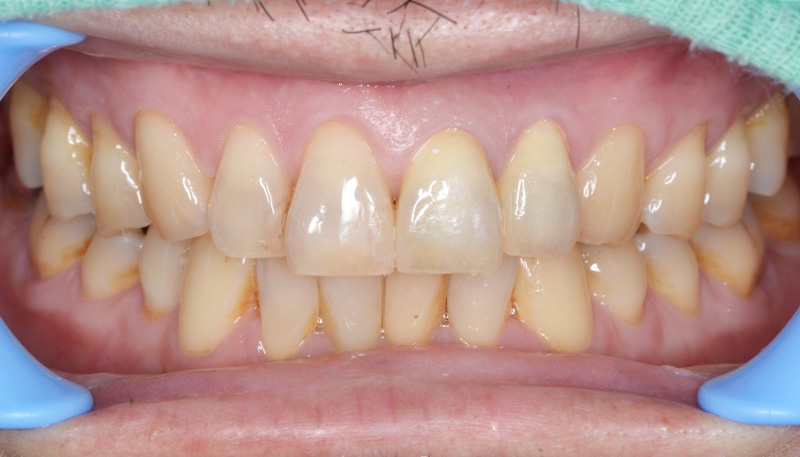

Case.06

歯並び矯正Case.05 歯並び矯正Case.05

歯並び矯正Case.05

主訴歯並びを変えて被せ物

もすべて綺麗にしたい

治療期間1年

治療費用2,545,400円(税込)

治療内容ワイヤー矯正

+セラミック治療

+ホワイトニング

治療のリスク破折の可能性